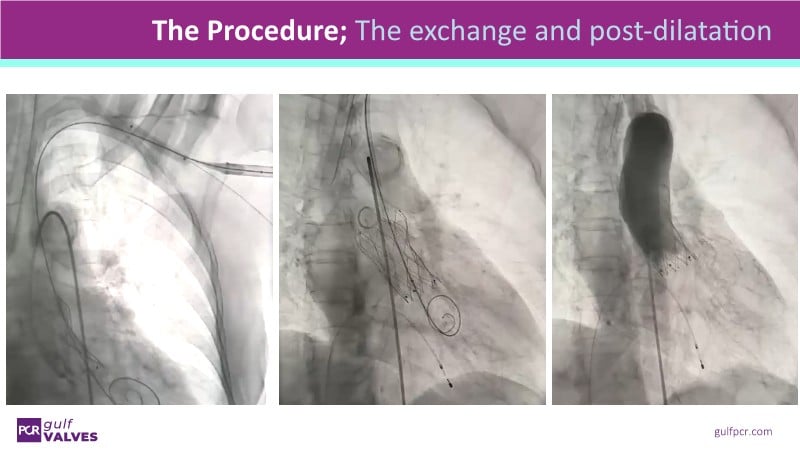

Discover a selection of cases showcasing the key features of the Navitor Valve System and its clinical applications. This session explores auxiliary access, the use of Navitor in alternative access and complex PCI, its performance in challenging peripheral anatomies, and innovative outcomes with the Vantage 30D system.